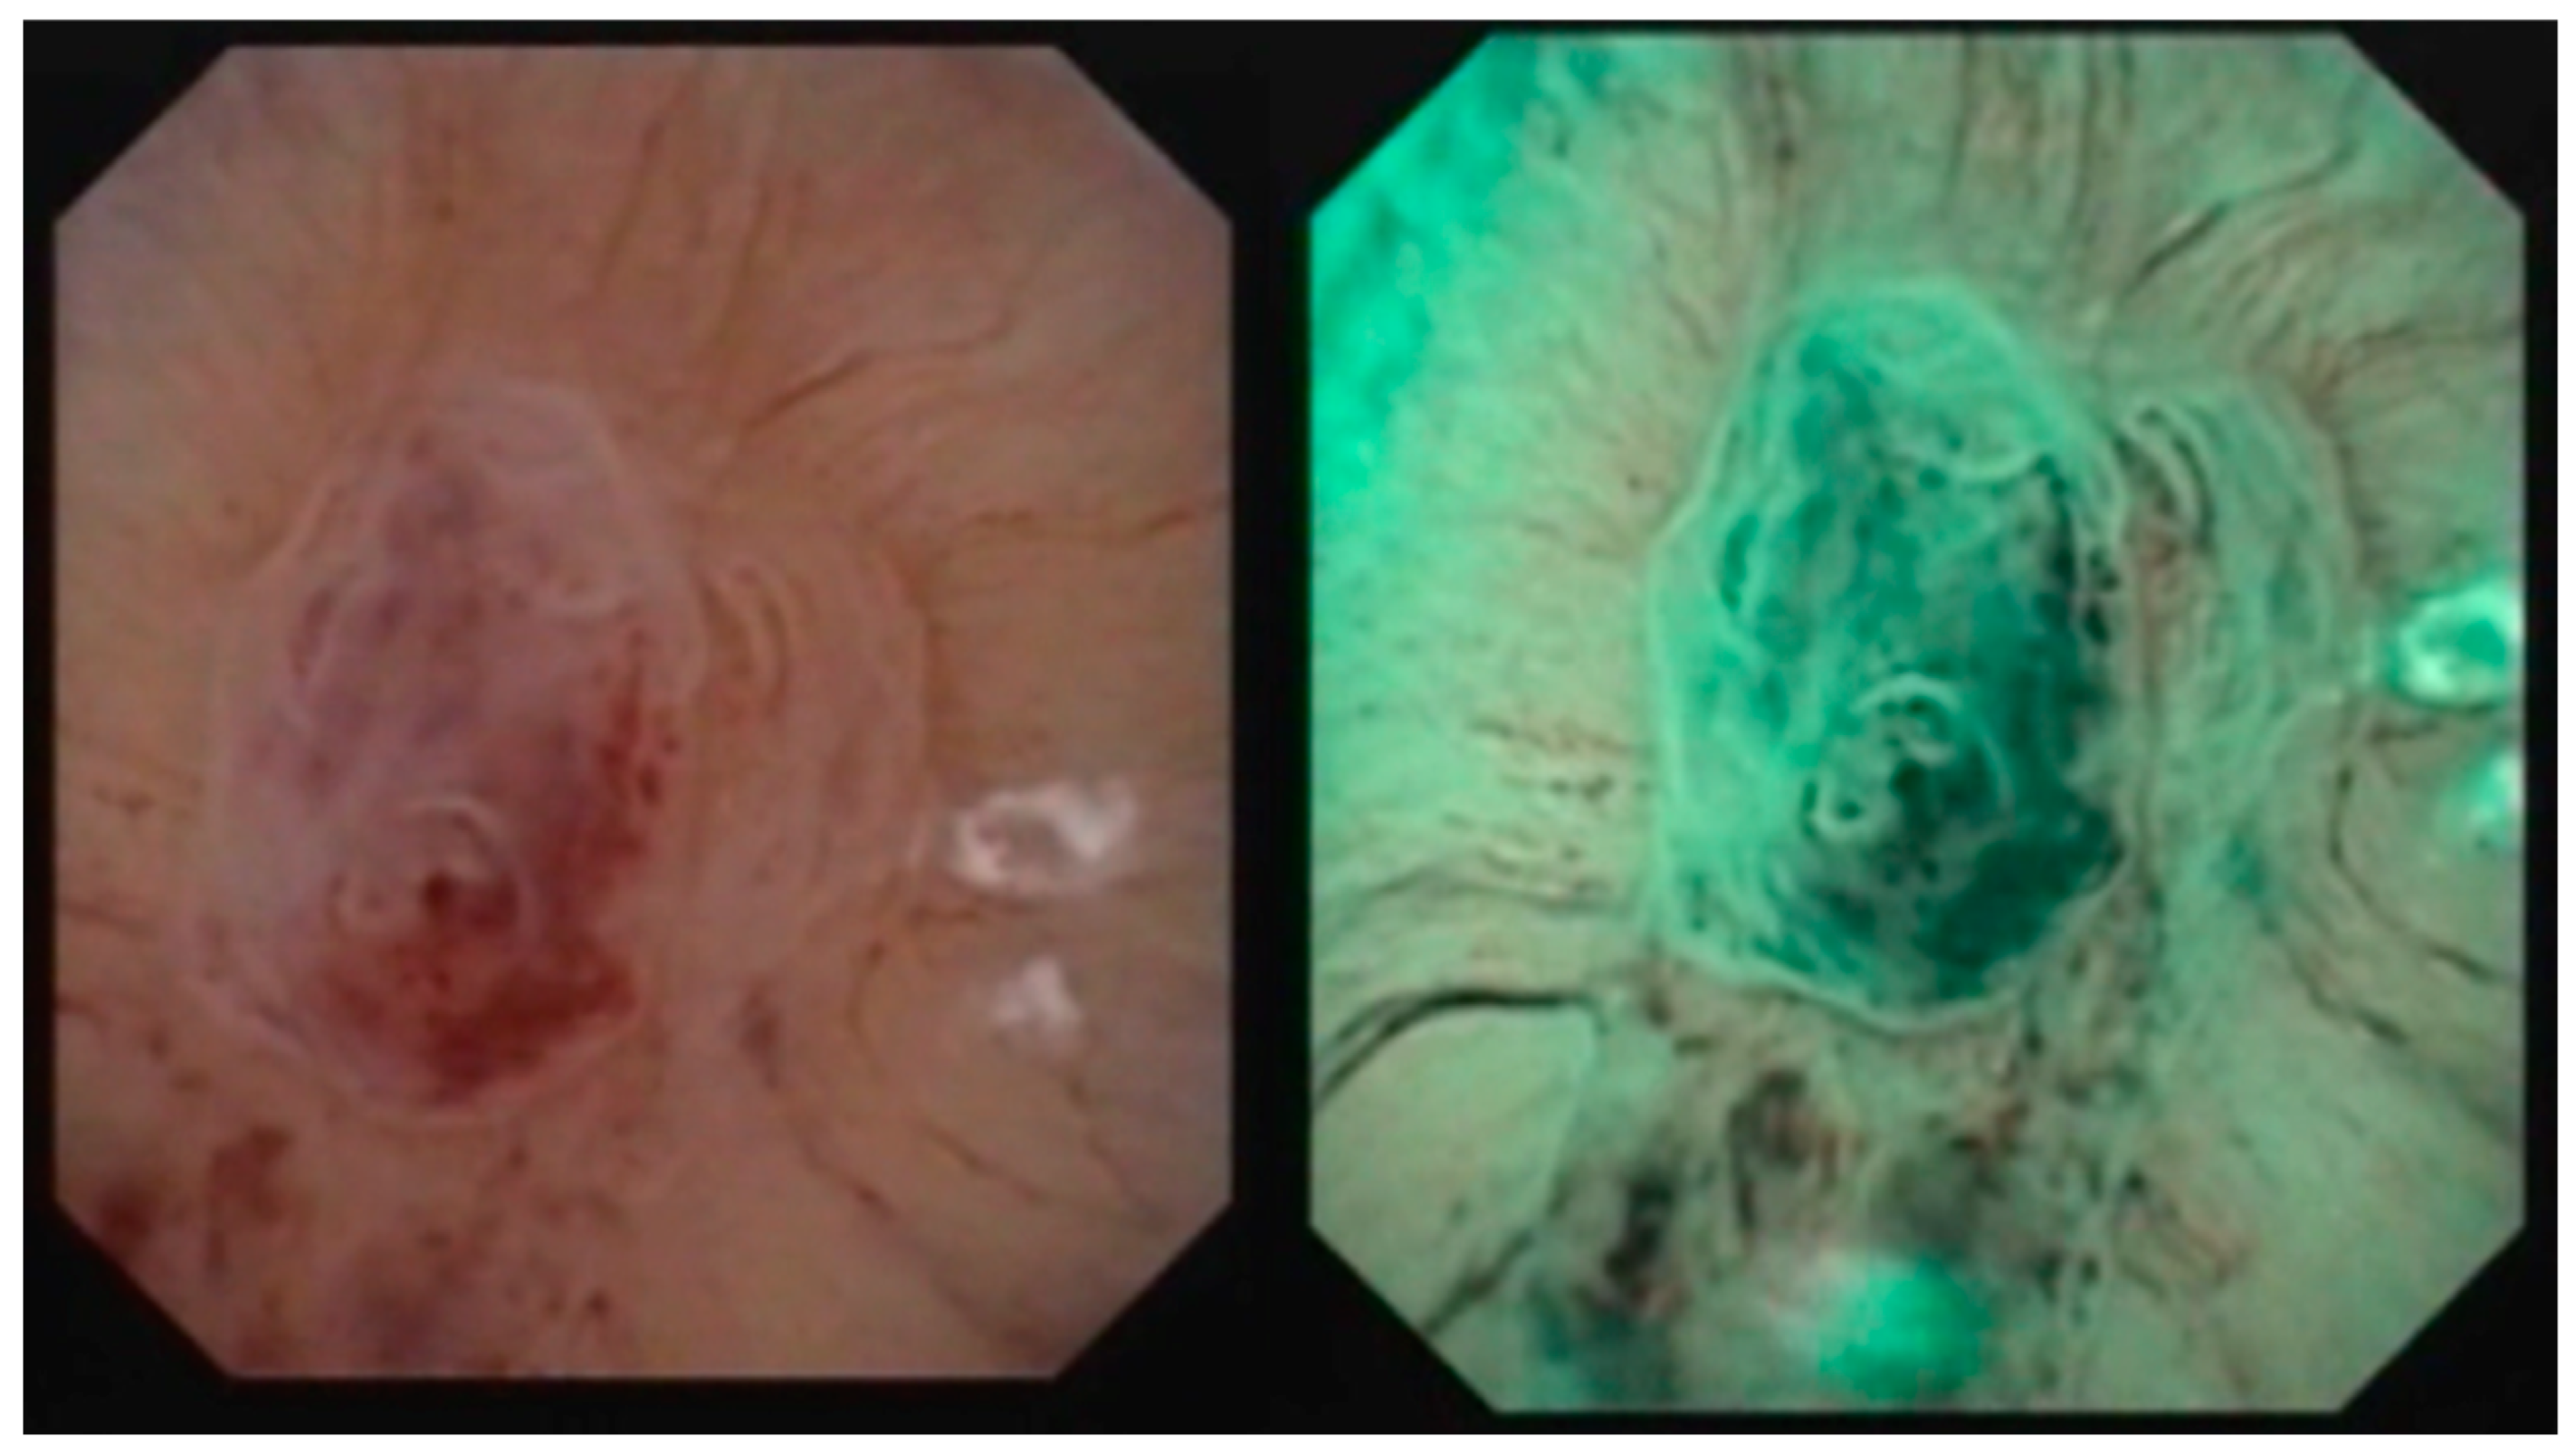

- Iordache, V.F.; Geavlete, P.A.; Georgescu, D.A.; Ene, C.V.; Păunescu, M.A.; Niculae, A.; Peride, I.; Neagu, T.P.; Bulai, C.A.; Bălan, G.X.; et al. NBI-assisted digital flexible ureteroscopy in transitional renal cell carcinoma—An evidence-based assessment “through the looking glass” of the pathological analysis. Rom. J. Morphol. Embryol. 2018, 59, 1091–1096. [Google Scholar] [PubMed]

- Meyer, F.; Al Qahtani, S.; Gil-Diez de Medina, S.; Geavlete, B.; Thomas, A.; Traxer, O. Narrow band imaging: Description of the technique and initial experience with upper urinary tract carcinomas. Prog. Urol. 2011, 21, 527–533. [Google Scholar] [CrossRef]